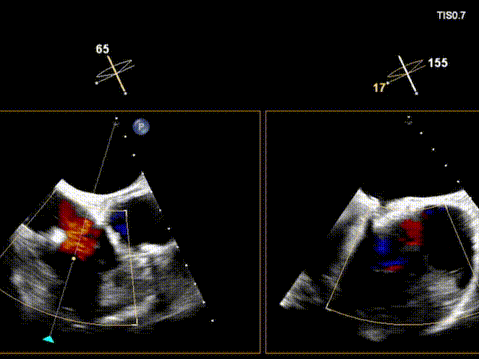

术前超声

术后超声